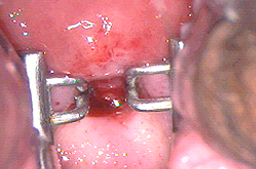

Consiste en la extirpación de un fragmento de cuello utilizando un electrodo con alambre (existen diferentes tamaños y formas) por el cual corre energía eléctrica de alta frecuencia (radiofrecuencia) Cuando es utilizado por un colposcopista experto, se utiliza la potencia de energía adecuada, la velocidad de corte adecuado y se seleccionan las pacientes con lesiones no muy extensas ha dado muy buenos resultados.